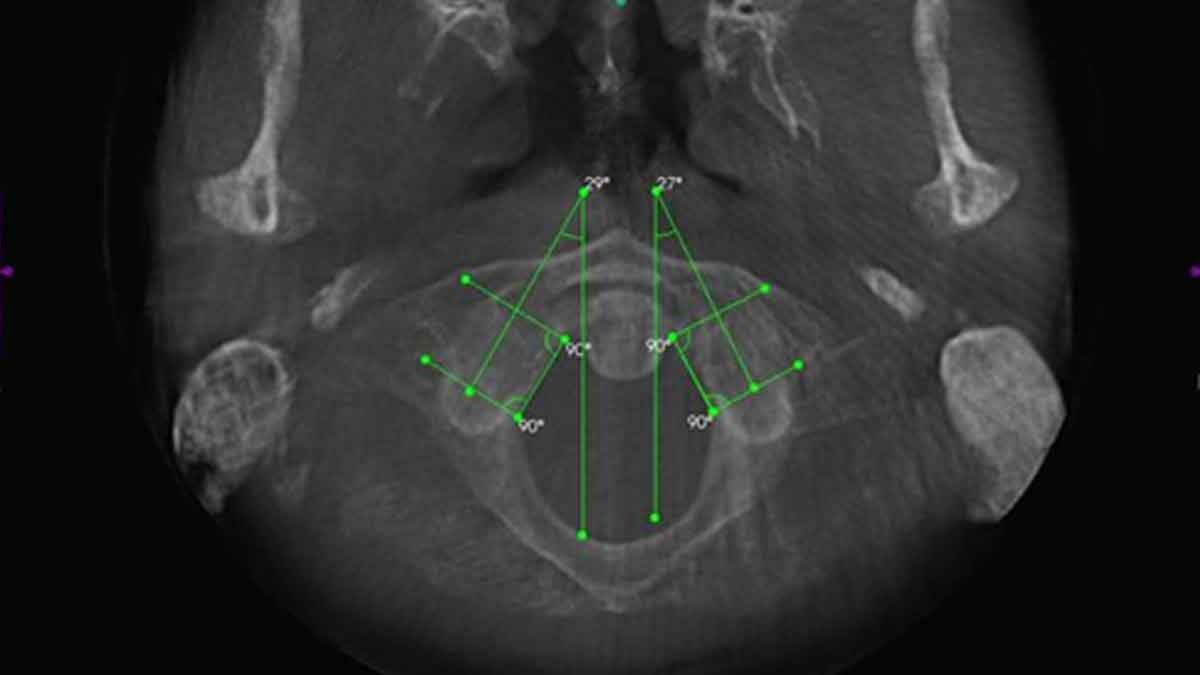

To see what CBCT images look like check out this video where Dr. Hall explains CBCT imaging technology and then goes over some of the views. Also, below you will find pictures of CBCT technology and real-life examples of articular spinal misalignments.

AXIAL VIEW OF FORAMEN MAGNUM AND ATLAS

This view allows the doctor to study the alignment of the upper cervical spine in a traditional APOM view. In chiropractic, the APOM is viewed from the posterior to the anterior to keep left and right right.